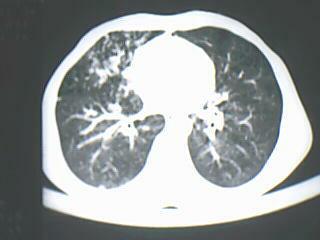

以下是引用随光逐影在2009-8-7 15:40:00的发言:[br]考虑右肺继发性肺结核并右肺上叶空洞形成,两肺支气管播散;不排除右肺上叶空洞内霉菌感染可能。

以下是引用jiangjing在2009-8-7 14:38:00的发言:[br]右上肺张力空洞,酐珞坏死灶,支气管扩张,多发播散灶,纵膈淋巴结显示,胸膜增厚---结核